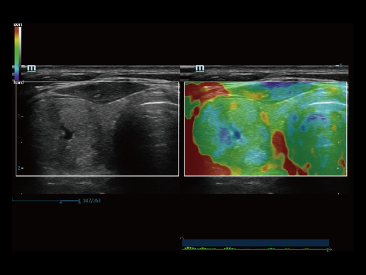

Since the company was founded, Mindray has been continuously exploring new ways to improve diagnostic confidence. Powered by the most revolutionary ZONE Sonography? Technology, Resona 7ŌĆÖs new ZST+ platform brings ultrasound image quality to a higher level by zone acquisition and channel data processing.